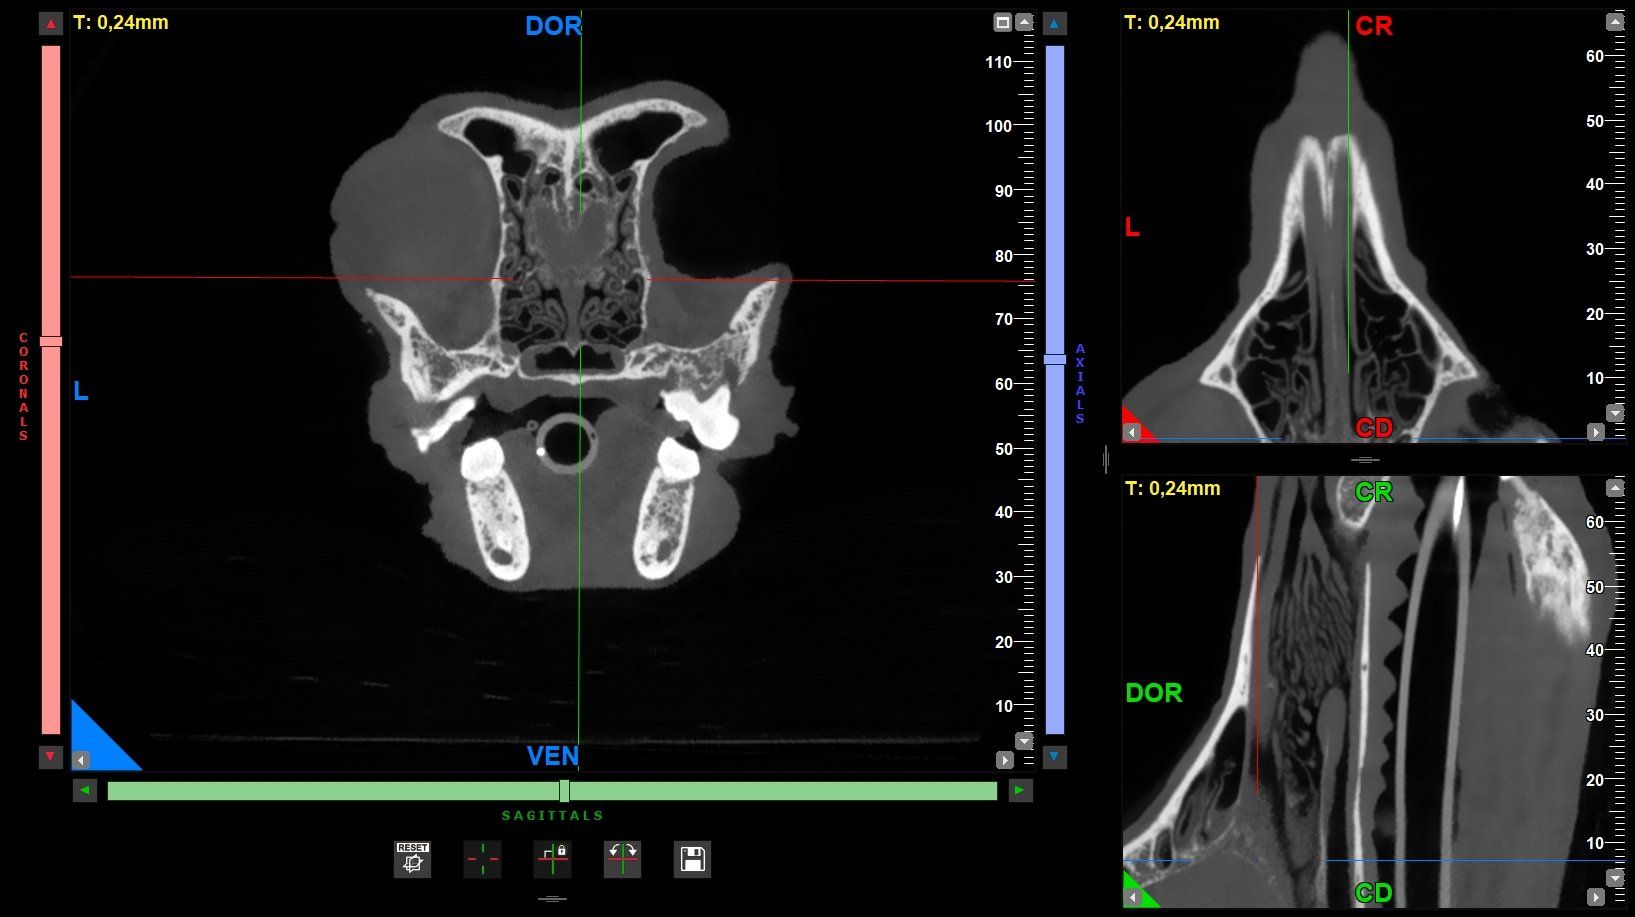

L’Ospedale Veterinario Città di Conegliano, in provincia di Treviso, mette a disposizione di tutti i propri pazienti un servizio di diagnostica radiologica avanzata, grazie al quale è possibile eseguire esami come la nuova TC di ultima generazione. Al servizio di radiologia digitale, infatti, oggi si associa la nuova TC con "cone beam technology".

L'esame TC consiste in uno studio completo che permette di visualizzare anche i più piccoli dettagli dell’anatomia del paziente. Si tratta di un esame rapido, indolore e del tutto non invasivo, e richiede solo la sedazione dell'animale.

L'esame TC è necessario in diversi ambiti medici tra i quali l’ortopedia, l’oncologia, l’odontostomatologia, la neurologia e molti altri ed è particolarmente utile per ottenere informazioni fondamentali per la cura dell’animale.